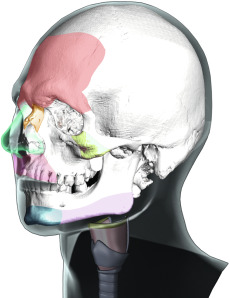

These differentiating features appear in the frontonasoorbital complex, the nose, the malar region, the upper lip, the jaw and chin complex, and the thyroid cartilage ( Fig. 8.1 ). The development of these structures under hormonal influence is not reversible, and thus these features, which determine a significant part of an individual’s facial gender, can only be approached and modified using surgery, always respecting the intrinsic architecture and anatomy of the craniofacial skeleton.

This area is quite possibly the greatest determinant of facial gender. The region encompasses the forehead surface, the supraorbital ridge (frontal bossing), the eye sockets, the frontomalar buttresses, the temporal ridges, and the frontonasal transition ( Fig. 8.2 ). The supraorbital ridge is almost invariably much more strongly developed in the male than in the female, although, typically, all of these areas are more pronounced and have greater bone volume in the male skeleton than in the female skeleton. The forehead contour in the female is higher, smoother, more vertical, and may be rounded to the point of forward protrusion. It determines the position of the eyebrows and the positioning of the periorbital soft tissues like the eyelids.

To better understand the jaw, it needs to be divided into the mandibular body, the mandibular angle and the ascending ramus ( Fig. 8.3 ). Generally speaking, the male jaw is larger, with greater body height and a broader ascending ramus. The mandibular angle formed by the body and ramus tends to be more acute in males, at times with everted gonial angles. The greater bone volume and vertical height are important factors when planning mandibular reshaping techniques in FGCS.

The male chin tends to be more square-shaped, with more pronounced and defined transitions between the chin and mandibular body, greater bone volume, and a more significant vertical dimension. Gender does not necessarily determine the position of the chin; that is, it is possible to find retro-positioned or over-projected chins in both men and women. However, a well-defined and projected chin may improve the overall aesthetics of the jaw-chin region.